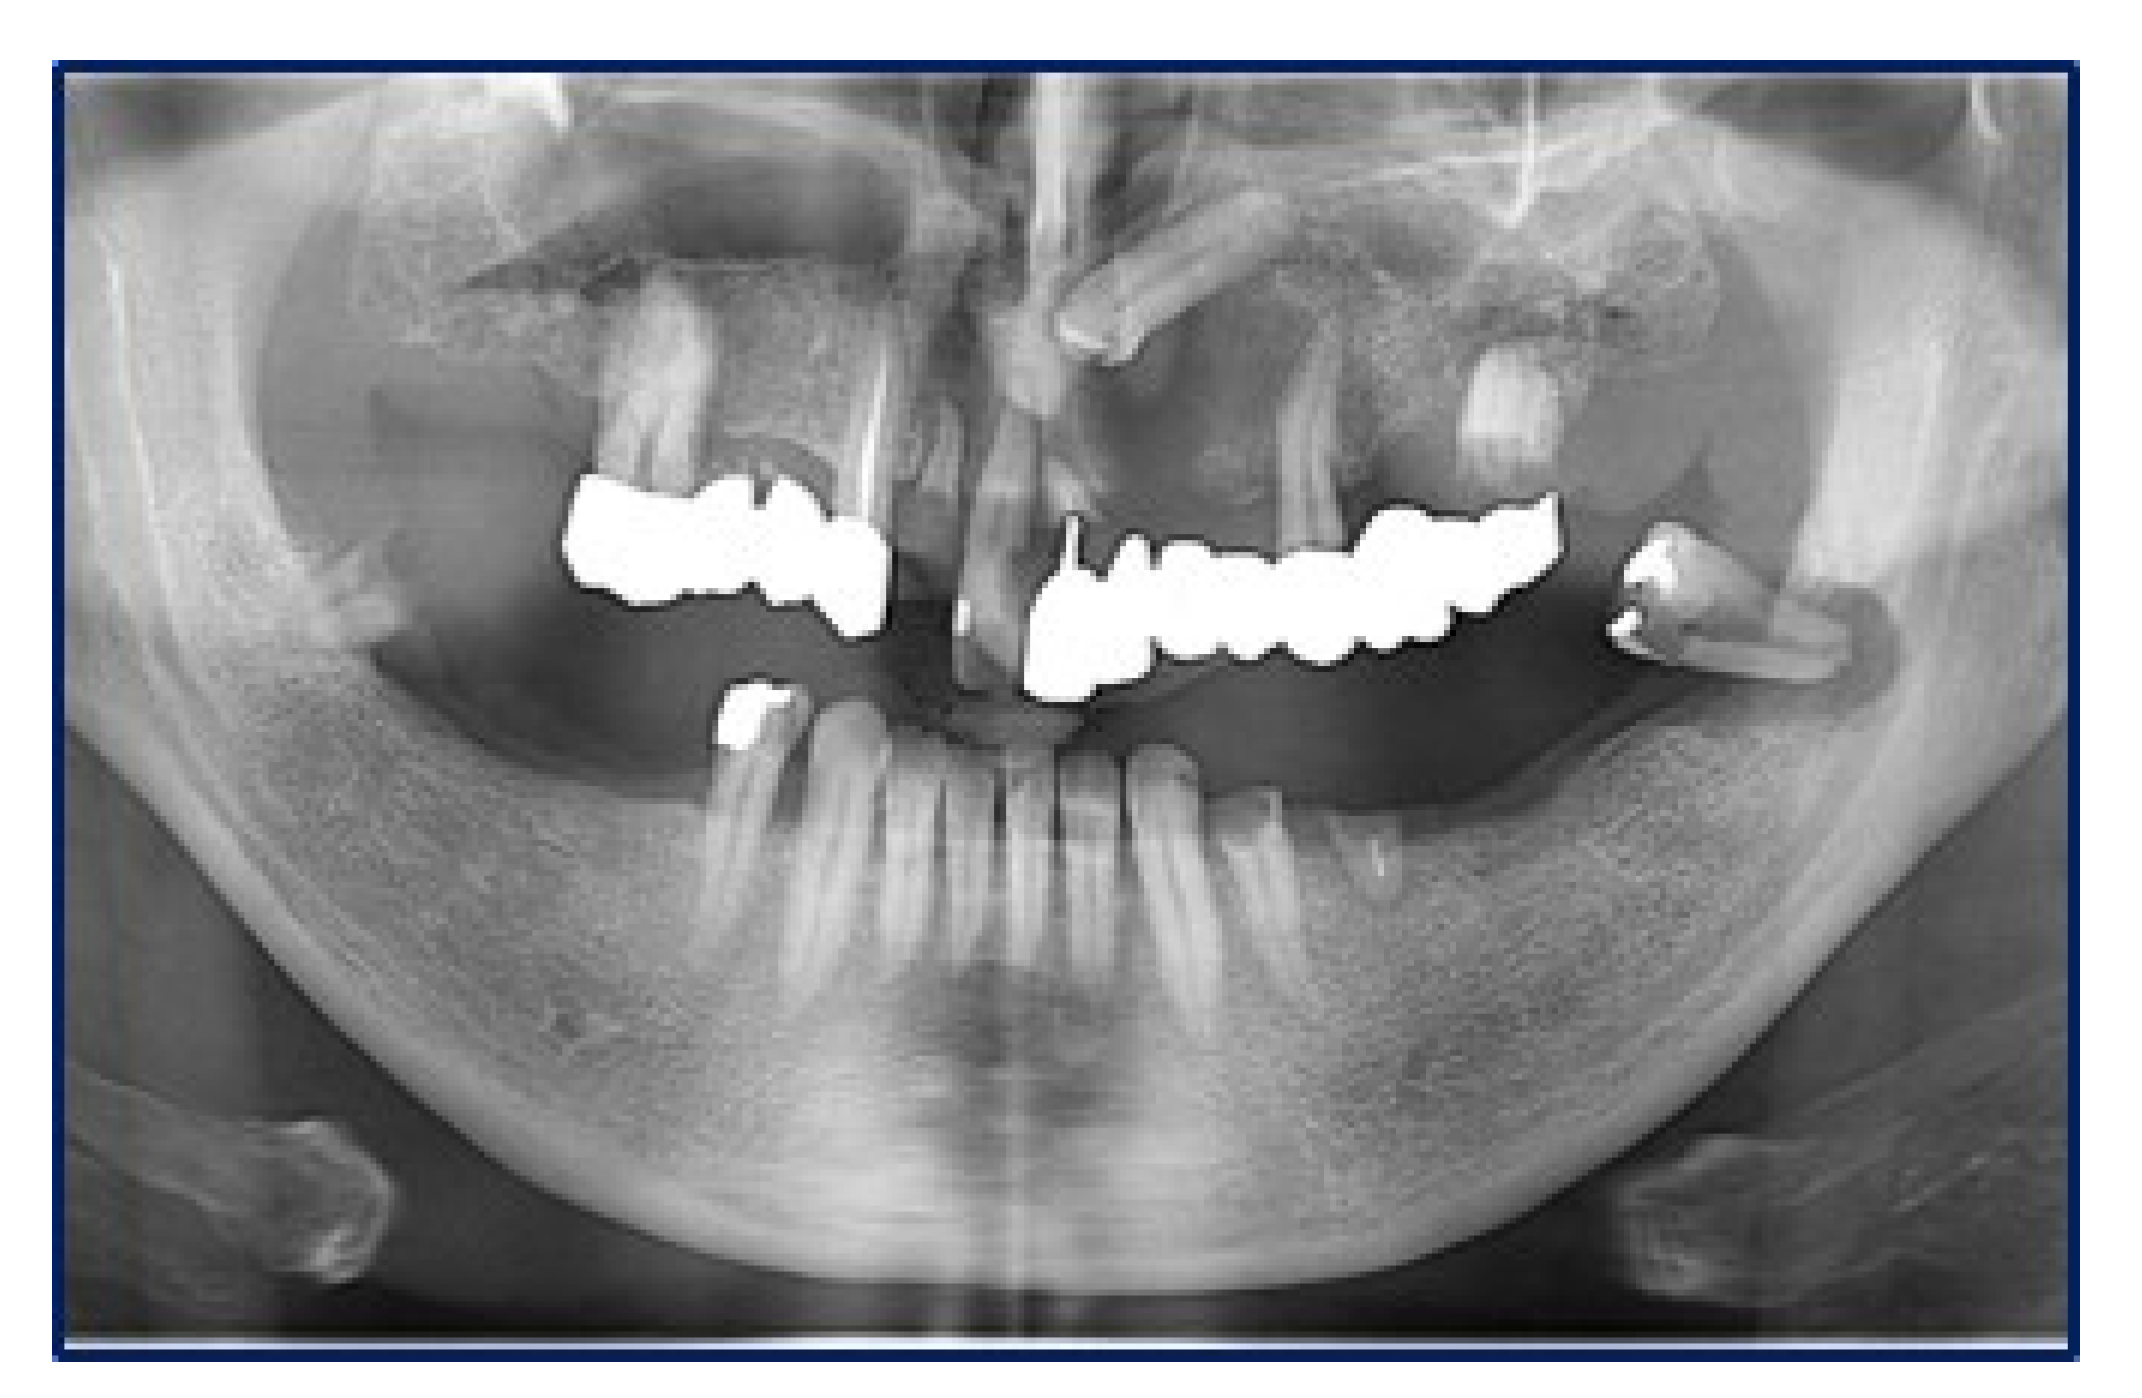

Panoramic radiograms (Figure 2) and CT-scans (Figure 3) highlighted maxillary and palatal bone involvement, while US and MRI of the head and neck were negative for relevant loco-regional lymphadenopathy. A PET scan, brain CT and abdominal US showed no metastatic deposits. On such bases, the diagnostic hypothesis was of primary oral MM, clinically staged as T4aN0M0 [6].

Figure 2.

Panoramic radiogram showing an osteolytic lesion of the left anterior maxilla with undefined borders, involving the periodontal ligament of 2.1 and 2.4 as well as the retained 2.3 tooth.